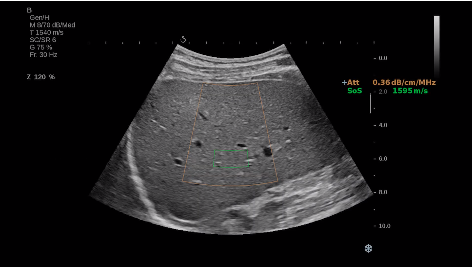

法國(guó)聲科影像(SuperSonic Imagine,SSI. Euroniex:FR0010526814)近日發(fā)表公告,宣布其研發(fā)的新一代“極速”超聲成像平臺(tái)(UltraFast Imaging),首次實(shí)現(xiàn)了肝臟的多項(xiàng)超聲定量評(píng)估新指標(biāo)同步檢測(cè),包括:Att PLUS,SSp PLUS和Vi PLUS等,基本涵蓋肝臟相關(guān)病理變化指征的如纖維化、脂肪變、炎癥等。據(jù)悉,此多項(xiàng)新技術(shù)新將搭載于新Aixplorer系列E超系統(tǒng)。